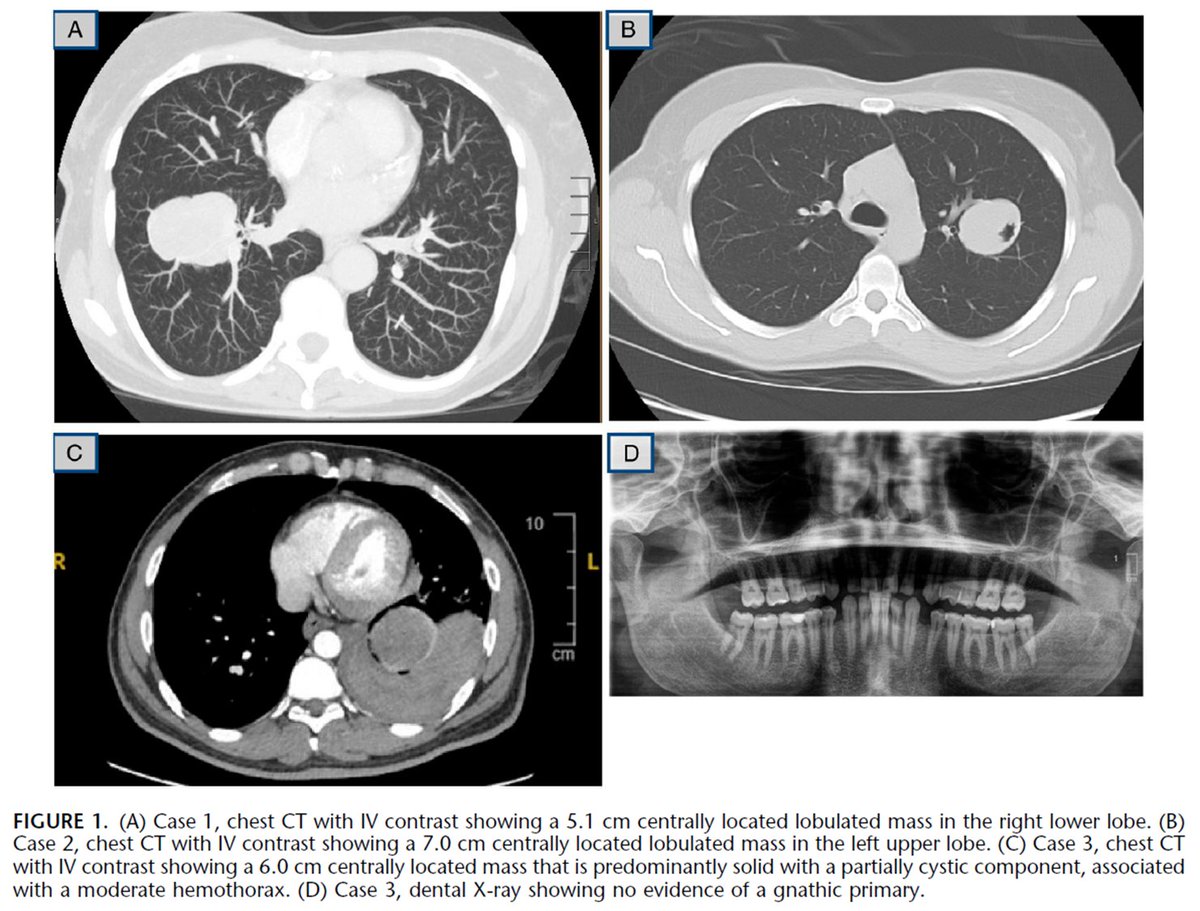

Just out in AJSP – a paper from our group describing a MAJOR new oddity.

Tumors that normally arise in the jaw from tooth🦷precursors (ameloblastoma) – but as lung primaries 🫁!

This was a neat collaboration b/w MSKCC, Mayo and UTSW where these cases were encountered independently, and we put our heads together with the help of original contributors and fellows to tackle this puzzle.

Time will tell if these are truly exceptional or have been underrecognized.

journals.lww.com/ajsp/fulltext/…